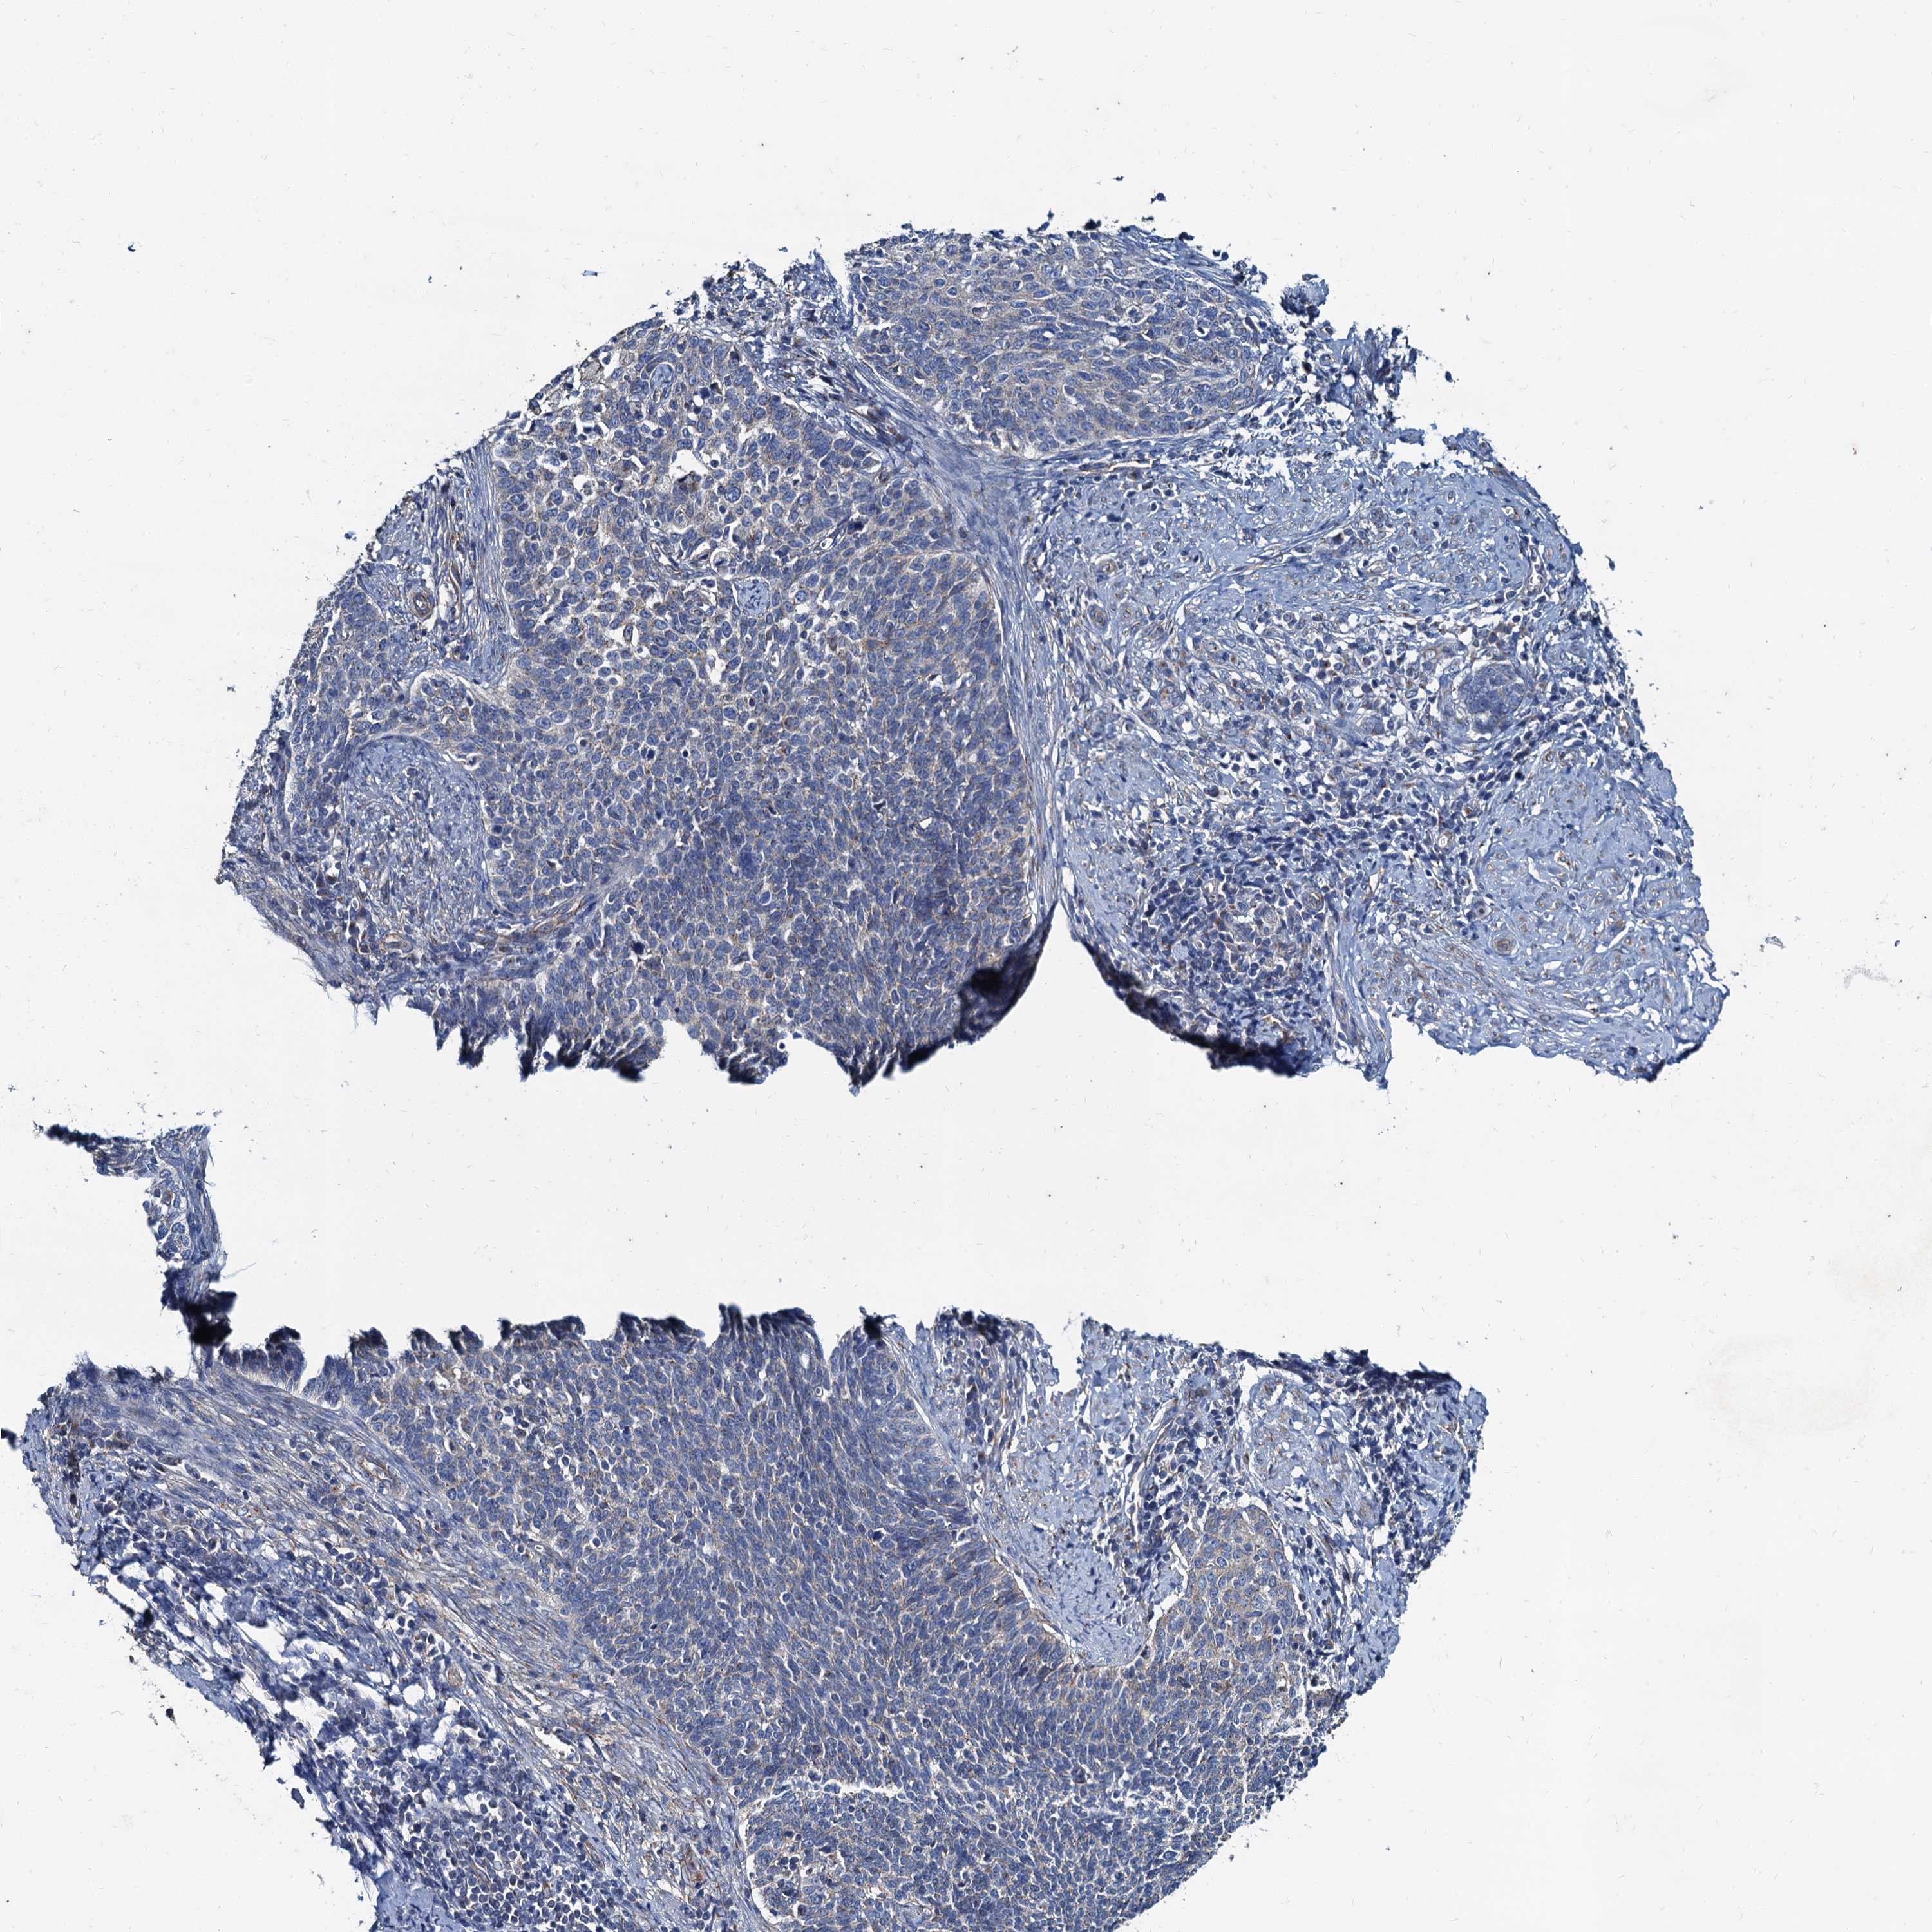

CERVICAL CANCER - Protein expressioni

A mouse-over function shows sample information and annotation data. Click on an image to view it in a full screen mode. Samples can be filtered based on level of antibody staining by selecting one or several of the following categories: high, medium, low and not detected. The assay and annotation is described here.

Note that samples used for immunohistochemistry by the Human Protein Atlas do not correspond to samples in the TCGA dataset.

Antibody stainingi

Antibody staining in the annotated cell types in the current human tissue is reported as not detected, low, medium, or high, based on conventional immunohistochemistry profiling in selected tissues. This score is based on the combination of the staining intensity and fraction of stained cells.

Each image is clickable and will lead to virtual microscopy that enables deeper exploration of all samples and also displays staining intensity scores, fraction scores and subcellular localization as well as patient and tissue information for each sample.

Antibody HPA041367

Antibody HPA076267

Staining

High

Medium

Low

Not detected

Intensity

Strong

Moderate

Weak

Negative

Quantity

>75%

75%-25%

<25%

None

Location

Nuclear

Cytoplasmic/membranous

Cytoplasmic/membranous,nuclear

Squamous cell carcinoma, NOS

Adenocarcinoma, NOS